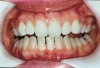

The whitening agents are available in various concentrations ranging from 10% carbamide peroxide (equal to 3.4% hydrogen peroxide) to 38% hydrogen peroxide. If the higher concentration agents contact the soft tissues, they can produce a chemical “burn” that turns the tissues temporarily white (Figure 1 and Figure 2). Although tissues quickly return to their normal color once they rehydrate, they may be mildly uncomfortable for a few hours. The patient may be distressed by the temporary appearance of the whitened soft tissues. A rubber dam or other protective barrier is mandatory to effectively seal off the tissues (Figure 3). In-office systems usually supply a light-cured resin in a syringe to apply around the cervical areas to confine the agent to the teeth (Figure 4 and Figure 5). In addition, flexible spreaders should be placed in the mouth to prevent the cheeks or lips from contacting the whitening agent.

Figure 1  Soft-tissue chemical burns near the left commissure of the mouth and along the free gingival margin due to exposure to the whitening agent.

Figure 2  Soft-tissue chemical burns near the left commissure of the mouth and along the free gingival margin due to exposure to the whitening agent.